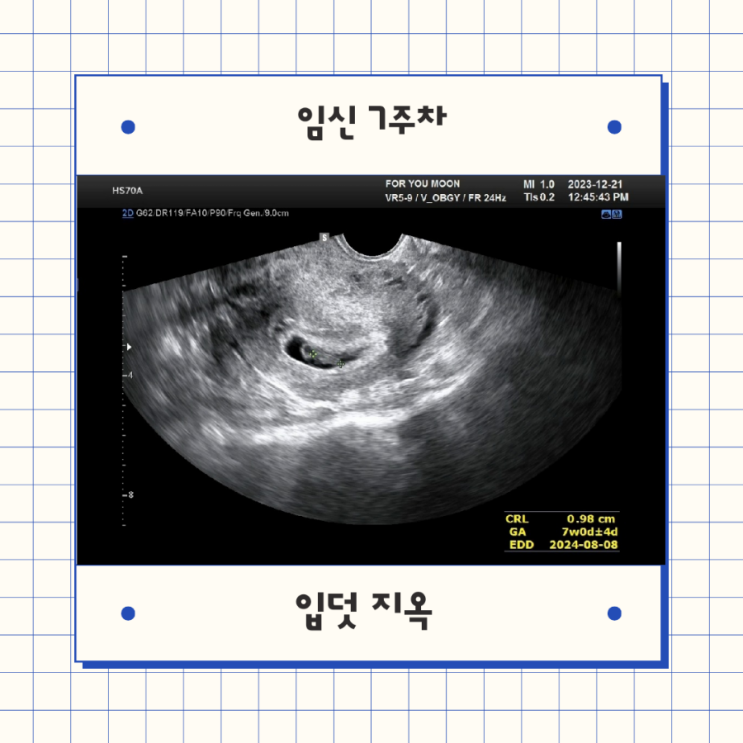

[임신 7주 차 증상] 셋째 임신에 대한 주변 반응 그리고 입덧 지옥의 시작

안녕하세요. 오늘은 임신 7주 차 이야기를 해보려 합니다:) 임신 7주 차 몸의 변화 임신 7주 차 초음파 검...